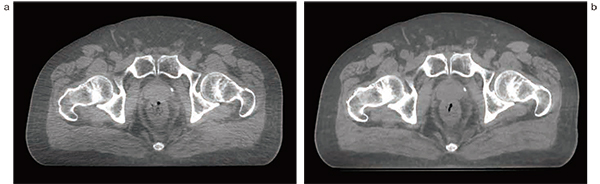

高精度放射線治療を行うには,直前に画像を取得し,患者の位置変位を計測・修正して治療を行うIGRTが必須である。TrueBeam Version2.7より,IGRTに必要なkVシステムによる位置照合cone beam CT(CBCT)において,散乱補正モデルおよび逐次近似法を用いた画像再構成技術であるIterative CBCT(iCBCT)が搭載された。これにより,画像のノイズの低減および散乱線アーチファクトなどの低減が図られることで,軟組織構造が良好に画像化され,高品質な画像での撮影が可能となった1)(図1)。特に,HyperArcでの位置照合時に脳転移病変周囲の脳溝や脳構造を確認できるため,安心して治療を行うことができる。

図1 Standard CBCTとiCBCTの比較

a:standard CBCT b:iCBCT